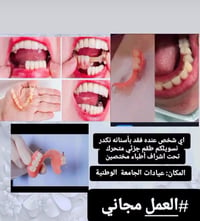

متوفر قلع بقايا جذور مجانا للتواصل ***********

مجاناً • قلع جذور • زراعة اسنان

مجاناً • قلع اسنان • حلة شارع ٤٠

قلع جذور • اسنان تالفة • خدمة اسنان

قلع مجاني • جذور تالفة • عيادات جامعة الفراهيدي

قلع مجانا • جامعة العين • أطباء اختصاص

قلع أسنان • قلع مجاني • جامعة العين

قلع أسنان مجاني • جذور متبقية • جامعة كربلاء

قلع أسنان • جذور أسنان • جامعة ذي قار

قلع أسنان • مجاني • كليه السلام

قلع جذور الاسنان • مجاناً • عيادات الجامعه الوطنيه ذي قار

قلع أسنان مجاني • جذور باقية • أسنان متحركة

قلع أسنان • جذور متبقية • علاج مجاني